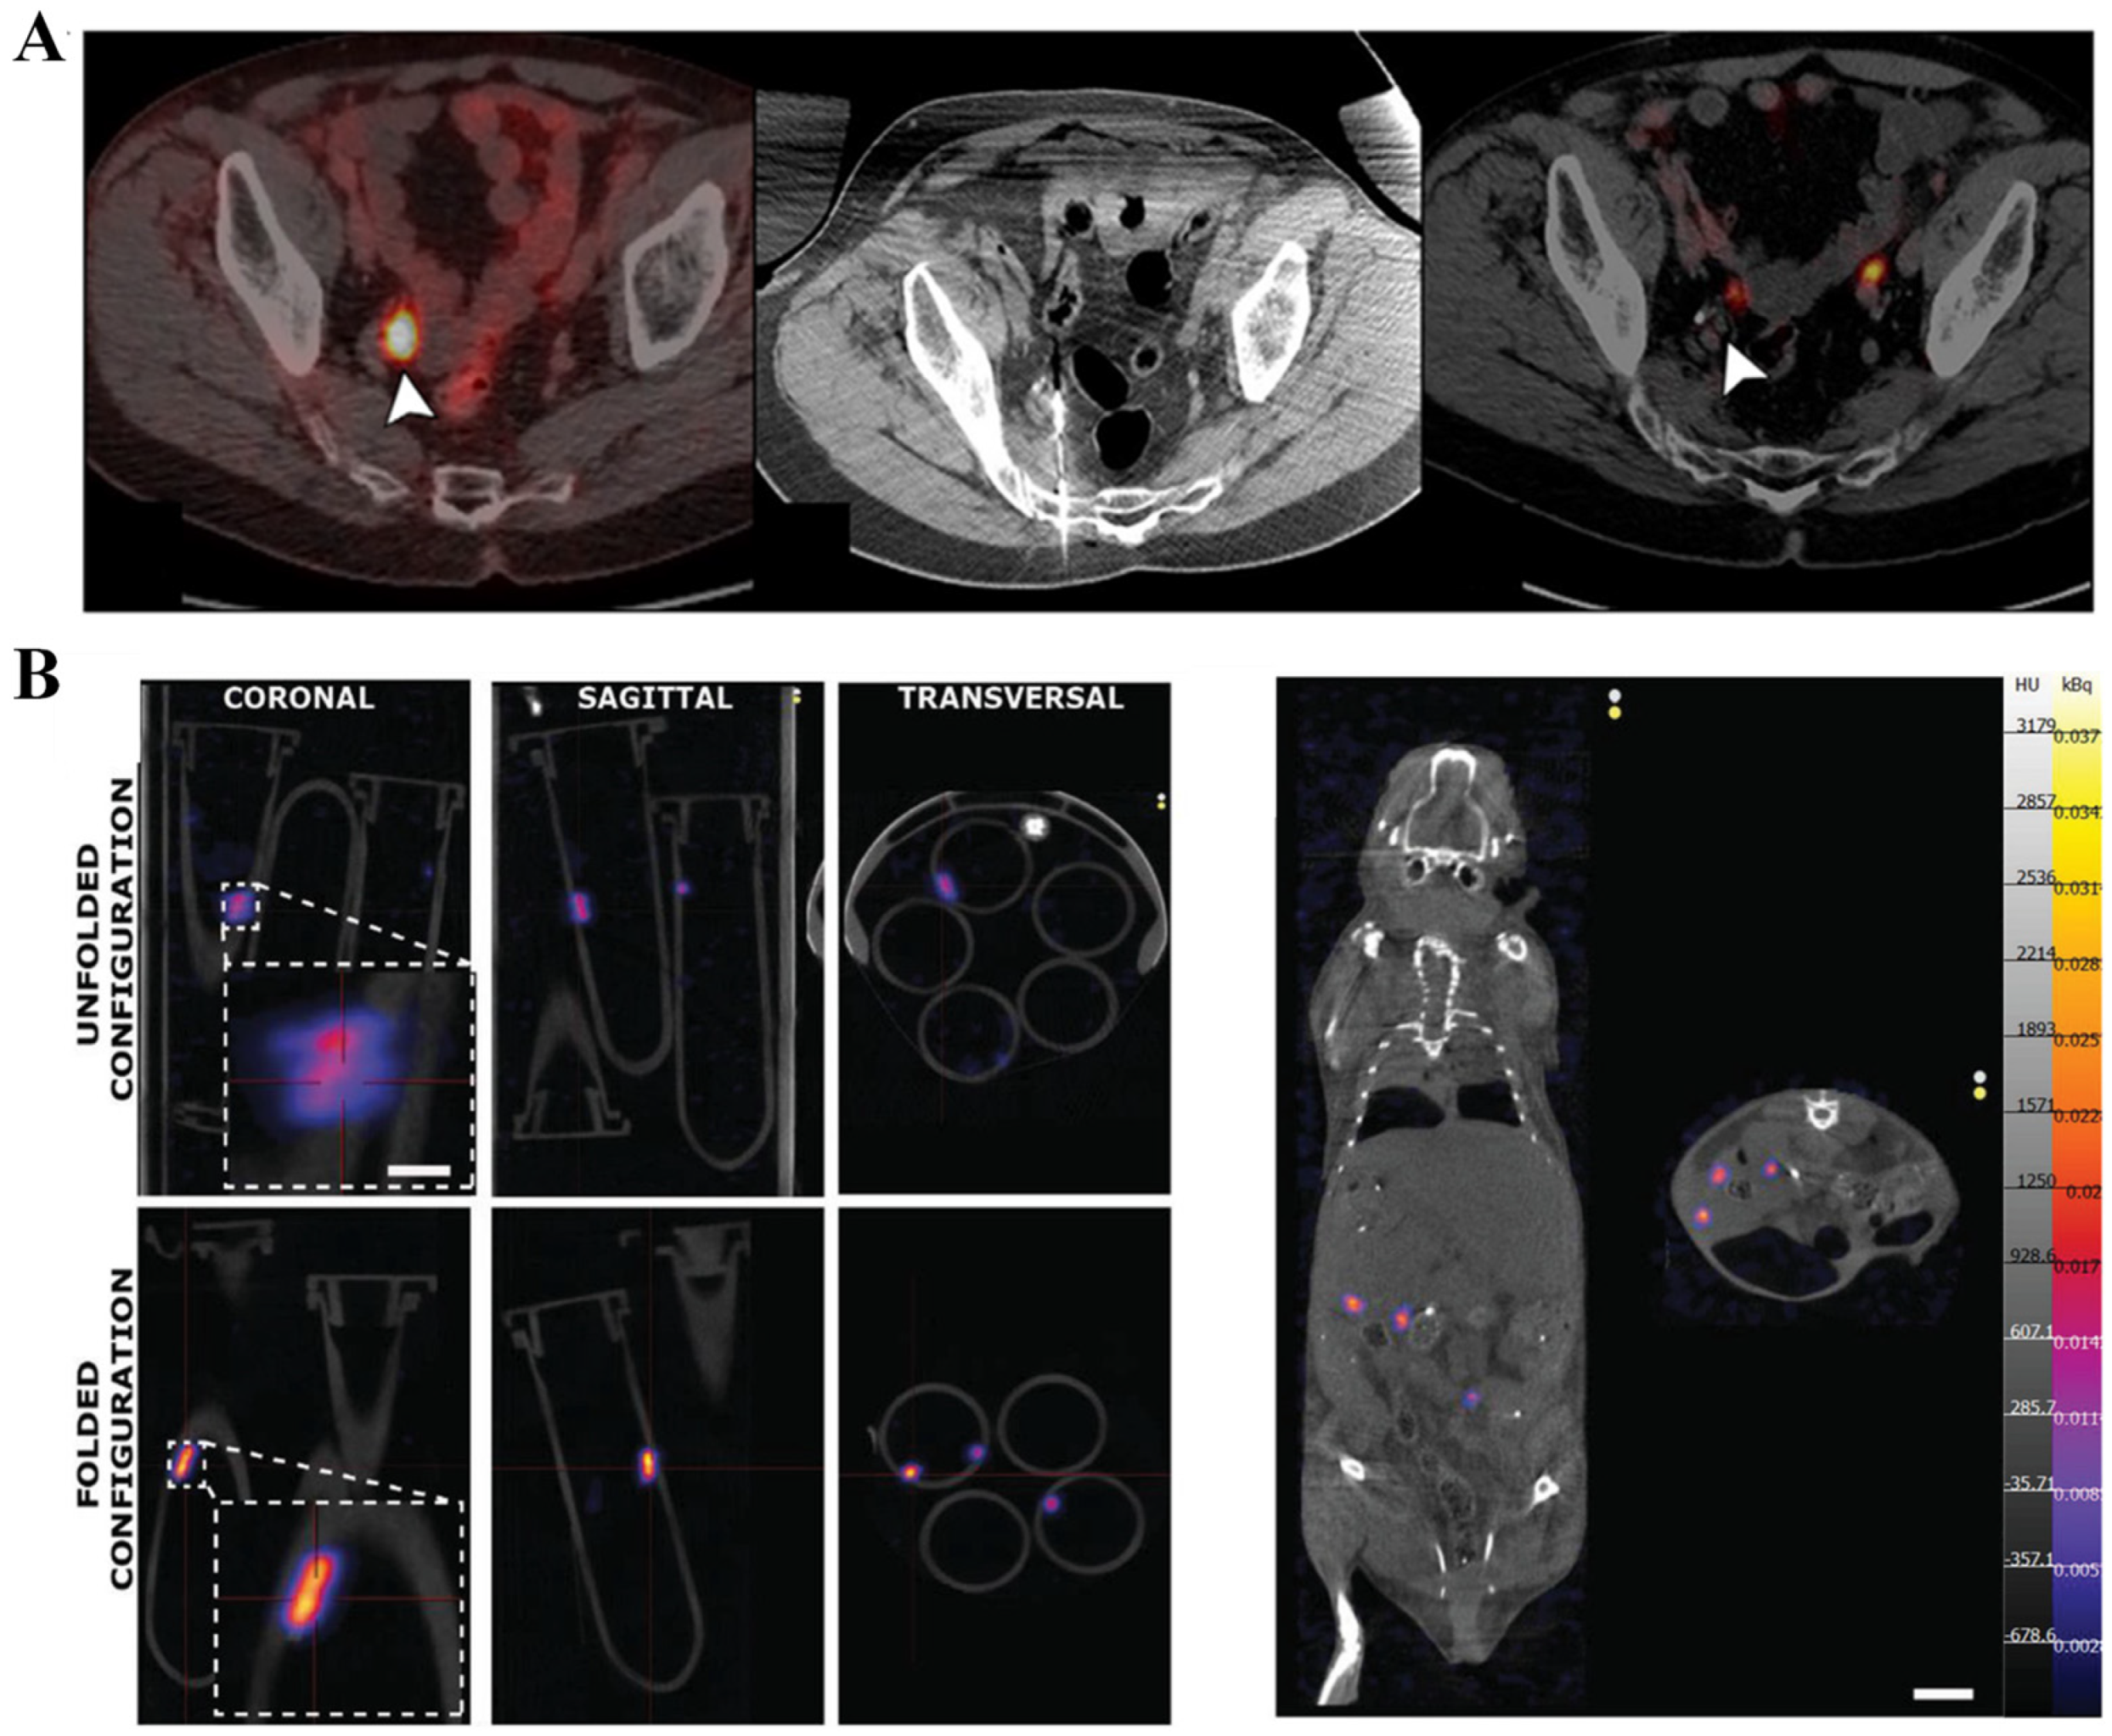

2.4. Ionizing Radiation-Based Techniques

2.5. Composite Imaging Techniques

- Iacovacci, V.; Blanc, A.; Huang, H.; Ricotti, L.; Schibli, R.; Menciassi, A.; Behe, M.; Pane, S.; Nelson, B.J. High-resolution SPECT imaging of stimuli-responsive soft microrobots. Small 2019, 15, 1900709. [Google Scholar] [CrossRef] [PubMed]

- Vilela, D.; Cossio, U.; Parmar, J.; Martinez-Villacorta, A.M.; Gomez-Vallejo, V.; Llop, J.; Sanchez, S. Medical imaging for the tracking of micromotors. ACS Nano 2018, 12, 1220–1227. [Google Scholar] [CrossRef] [PubMed]